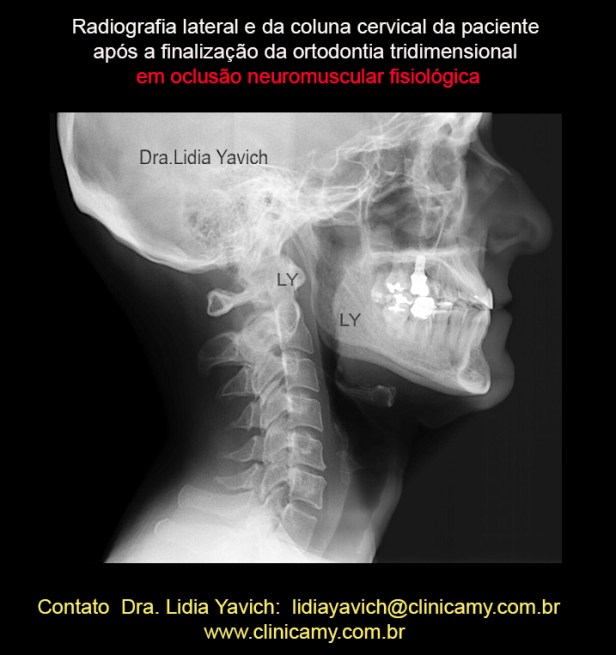

Radiografia lateral e da coluna cervical da paciente após a finalização da segunda fase do tratamento mediante uma ortodontia tridimensional e reabilitação neuromuscular fisiológica.

Radiografia lateral e da coluna cervical da paciente após a finalização da segunda fase do tratamento mediante uma ortodontia tridimensional e reabilitação neuromuscular fisiológica.